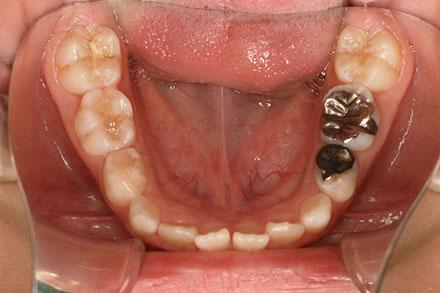

受け口を気にされ、他院からの紹介で来院された患者さんです。

小学2年生、生え変わりの時期から小児矯正を開始しました。

小児矯正で前歯の咬み合わせを改善し、

永久歯列完成後の中学生から非抜歯治療にて本格矯正を開始。

配列し仕上げました。